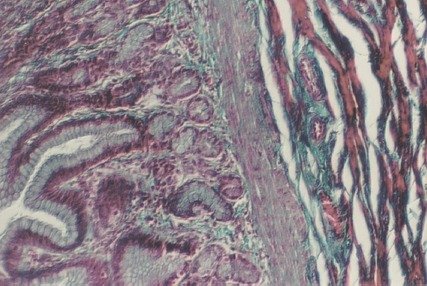

The next layer after the mucosa and muscularis mucosa is the submucosa, seen as connective tissue. It is similar to that in the esophagus. No glands are seen in the submucosa of the stomach. The following photo illustrates these regions.

Slide 52 is a section through the pyloric region of the stomach. It contains the basic structure of the glands in the fundus, except that parietal and chief cells are replaced by MUCOUS NECK CELLS. The following photo shows the mucosa and lamina propria in the pylorus. Note that the Gastric PITs are deeper. The second photograph shows the muscularis mucosa and submucosa.

Find the underlined regions on the photographs below